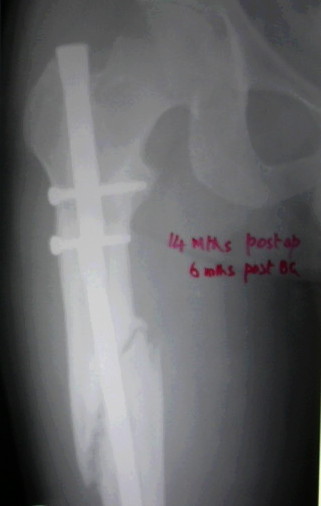

Failure to close 4/4 cortices 6 months post-op definitely meets definition criteria of non-union. Obviously, fixation has failed in this case and needs to be achieved via exchange nail.

Tough to tell from these x-rays, but fx ends appear sclerotic with bridging callus partially present - likely hypertrophic non-union, but you can do a bone scan to confirm viability.

VMI> Kindly note. a) the nail is going towards the medial aspect

VMI> of the lower end thus causing a 5* varus at the # site. b) there

VMI> is a slight overiding causing a centimeter of shortening.

It is agreed by almost all that this is a hypertrophic nonunion.

Ajit >>Also, there is insufficient callus to suggest a hypertrophic nonunion after 14 mths. As

Ajit >>mentioned by you the first surgeon has already opened the fracture site and probably

Ajit >>devitalised/ stripped the femur of its perisoteum. Adding bone grafts will surely help.

VMI- OK It is not hypertrophic but normotrophic nonunion. Mangal has already said so. Though the first surgeon has devitalised the femur, that was 14 mths ago. By the way, the second surgery (may be the same surgeon) 5 months ago may also have done some harm. Anyway there is no need to do bone grafting if everything is done closed.